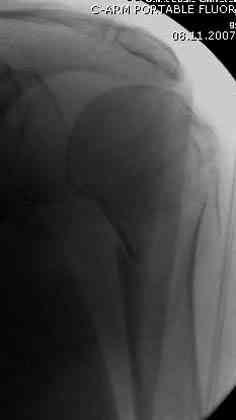

Наш недавний случай перкутанной фиксации "методом

Сиэтла" спицами 2.8 мм с резьбой на конце.

Головка плечав небольшом варусе или это проекционное?

-Головка плеча в небольшом варусе или это

проекционное?

Да, там имеем небольшой варус, надеемся, что в будущем проблемы не будет.

Из-за большого обьема конечности доступ к бугорку был затруднен, предварительно зафиксированный шуруп не удержал бугорок, поэтому фиксацию провели толстыми нитками. Состоятельность фиксации бугорка обычно проверяем во время операции, под рентген контролем проводится движения конечности, особенно приведение.